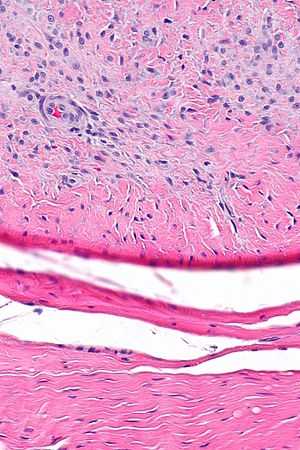

|

Palmar fibromatosis. H&E stain. | |

| LM | poorly demarcated, usu. multiple lesions/multiple nodules, composed of bland spindle cells in dense collagen; spindle cells have pale grey cytoplasm and a pale ovoid nucleus with small round nucleolus, +/-giant cells (rare) |

- Poorly demarcated, usu. multiple lesions/multiple nodules.

- Composed of bland spindle cells in dense collagen.

- Pale grey cytoplasm (moderate quantity).

- Pale ovoid nuclei with small round nucleoli.

- Giant cells - rare.

- No nuclear atypia.

- Mitotic figures - rarely present, none atypical.

- May see Pacinian corpuscle (AKA lamellar corpuscle) as an incidental finding.